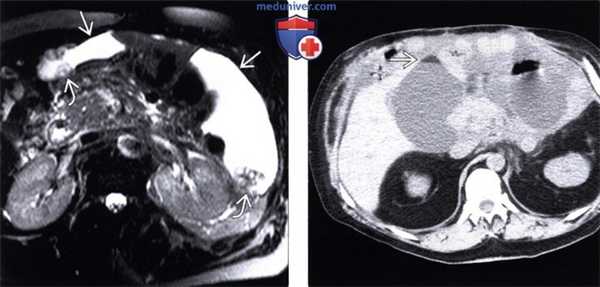

(Слева) На аксиальной Т2 МР томограмме с жироподавлением определяются осумкованные скопления дающей гиперинтенсивный сигнал жидкости. Обратите внимание на отдельно расположенные узлы в асцитической жидкости, отображающие тот факт, что асцит является «злокачественным» и возник в результате метастатического поражения брюшины при первичном раке аппендикса.

(Справа) На аксиальной КТ без контрастного усиления у пациента после трансплантации тонкой кишки определяются уровни «жидкость-жир» в скоплениях жидкости, которые отражают ее хилезную природу — результат утечки лимфы из лимфатических сосудов тонкой кишки.